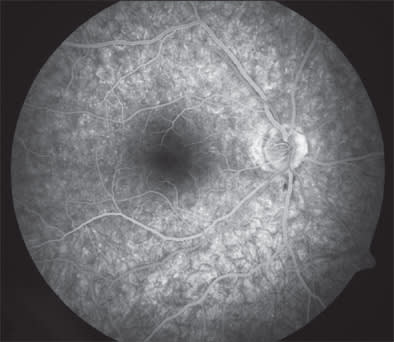

Inflammatory causes of photopsias are due to outer retinal or photoreceptor irritation from focal infection or inflammation. Flashes of light have been described in ocular toxoplasmosis7 and birdshot chorioretinopathy/vitiligo chorioretinopathy8 and in the spectrum of diseases that includes acute zonal occult outer retinopathy (AZOOR), multiple evanescent white dot syndrome (Figure 2), acute idiopathic blind-spot enlargement syndrome, punctuate inner choroidopathy, multifocal choroiditis and panuveitis, and acute macular neuroretinopathy.9-12 In AZOOR, photopsias are a frequent and important diagnostic symptom, accompanying visual loss or visual defects in up to 70% of eyes. Photopsias can either precede or follow onset of visual loss. They have been described as occurring in the field of the visual loss with the quality of flickering or shimmering.13 An antecedent viral-like illness has been described in association with the onset of most of these conditions.

Figure 2. Patient with multiple evanescent white-dot syndrome (MEWDS) and symptoms of unilateral photopsia.